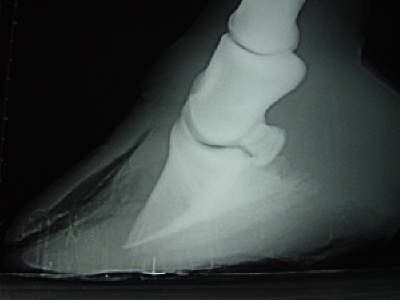

Röntgenbild zu diesem Fall. Hufbeinrotation und großflächige Ablösung der dorsalen Wand. Der Reissnagel zeigt die Strahlspitze an.